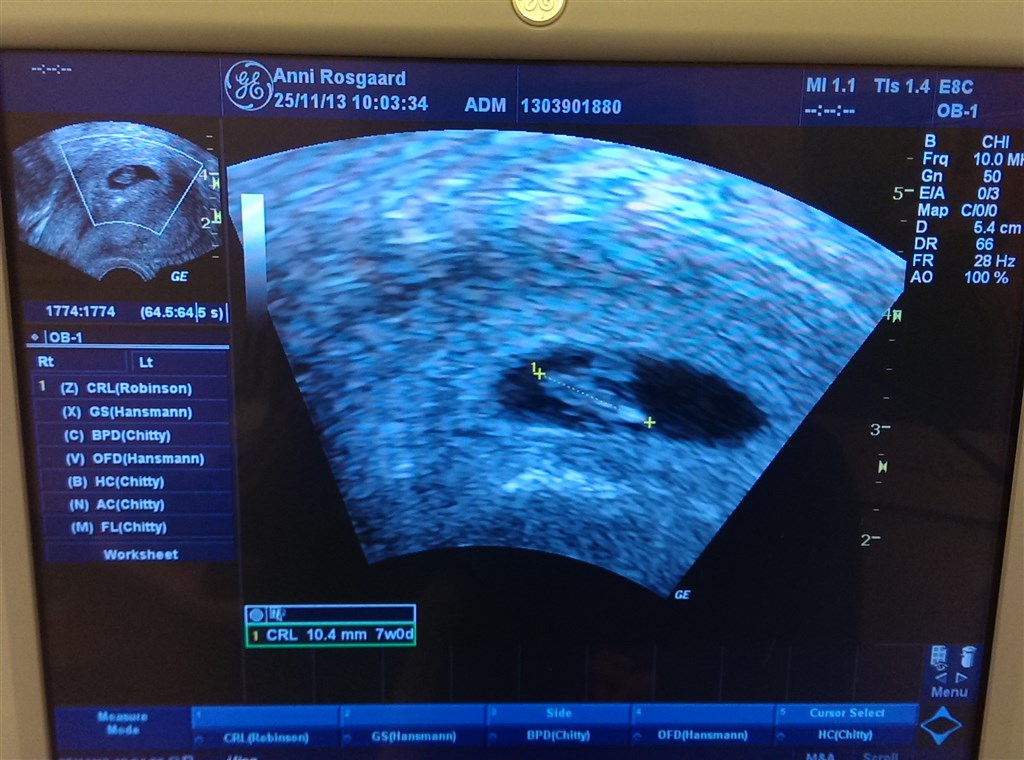

Ja, som overskriften siger er jeg netop hjemvendt fra scanning nede på klinikken

Jeg er idag 7+0, og det passede også med bebses størrelse.. Vi så meget klart hjerteblink, og fik bekræftet at der kun var én

Her er vores bebs